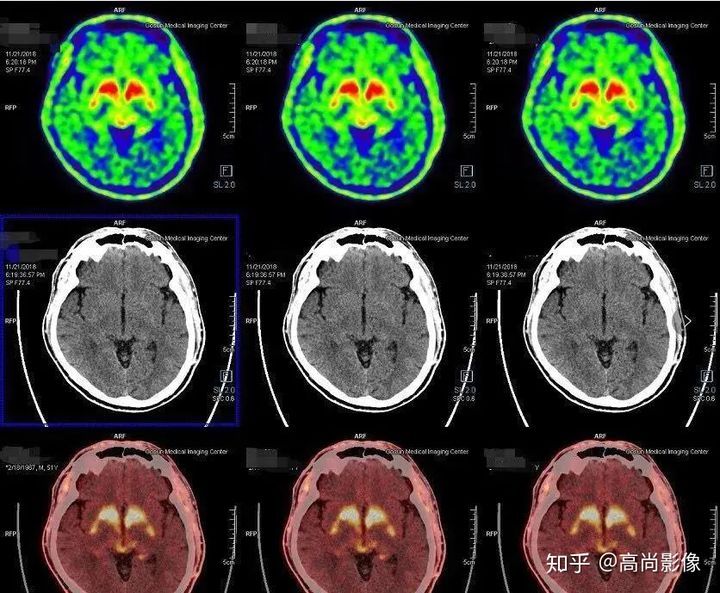

多巴胺轉(zhuǎn)運(yùn)體顯像可以幫助鑒別診斷帕金森和良性震顫,具有良好的診斷效能。

雙側(cè)尾狀核、殼核多巴胺轉(zhuǎn)運(yùn)體分布對稱、均勻

相比之下,童大媽就沒有這么幸運(yùn)了。除了右邊身子總是抖動,童大媽還有嗅覺障礙、動作緩慢等癥狀。童大媽的PET/CT檢查結(jié)果符合帕金森的表現(xiàn),為臨床診斷提供了重要依據(jù)。

雙側(cè)尾狀核多巴胺轉(zhuǎn)運(yùn)體分布對稱,左側(cè)殼核后部多巴胺轉(zhuǎn)運(yùn)體分布較對側(cè)明顯減少,結(jié)合童大媽癥狀,先考慮帕金森。